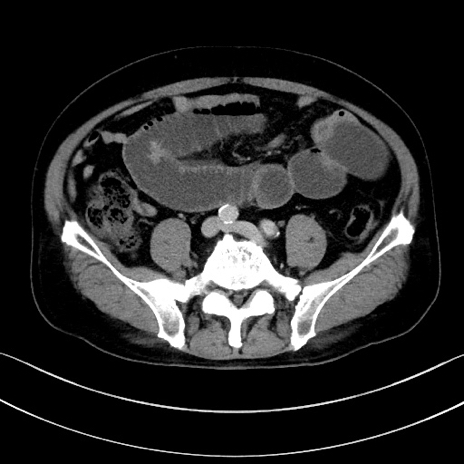

冠状断像